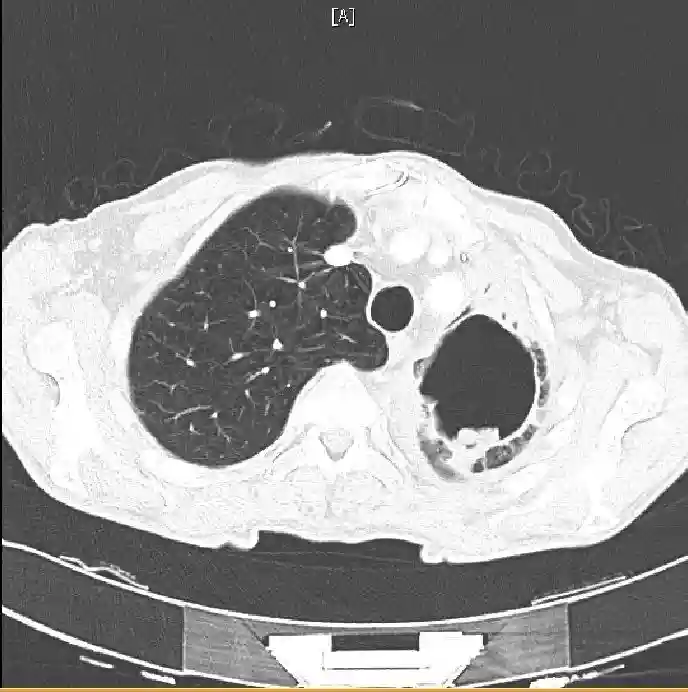

基于胸部X线片(图1)和计算机断层扫描(CT)(图2和3),做了进一步的实验室检查,并进行了支气管镜检查:

图2仰卧位CT扫描。